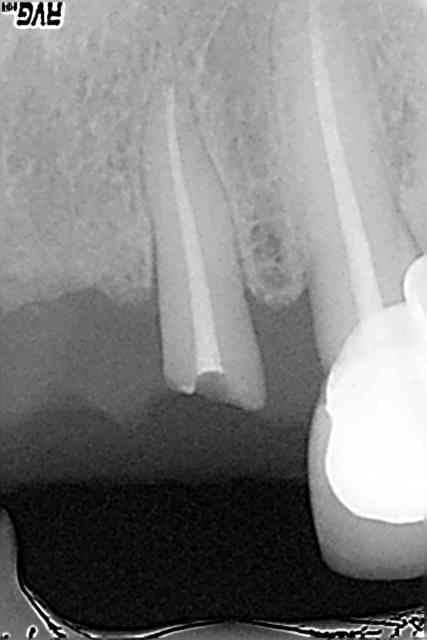

femme, 62 ans, santé RAS, qui arrive avec un bridge (fait par le confrère que j'ai remplacé il y a 2 ans) 11-(21)-22 mobile. 22 fracturée, je dépose, fais un provisoire.

Ce qui est sûr, c'est que je n'irai pas mettre un bridge sur cette latérale. Et même une couronne unitaire, j'hésiterais: trop grêle. Pas de ferule effect, racine trop courte. Bref tout pour plaire.

Vue l'état du tenon sur la 24 et le niveau d'os sur 27 le bridge secteur 2 risque de pas durer longtemps.

La 16, 15 et 14 carie sous gingival.

Pas faux (fracture céramique sur 23 aussi: il y'a quelque chose qui déconne dans l'occlusion de cette reconstruction).